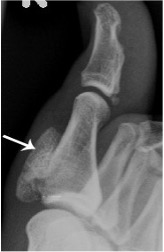

Osteochondroma of first proximal phalanx (arrow)

Osteochondroma

- Cartilage-capped exostosis seen as a bony outgrowth

- Cartilaginous component invisible on plain radiographs unless calcified

- Rarely, the cartilage cap may undergo transformation to malignant chondrosarcoma; cartilage cap thickness > 2cm is suspicious and usually assessed on MRI

- Pedunculated, subungual exostoses on the distal phalanx of the hallux are common and usually have a cartilaginous cap, classifying them as osteochondromata